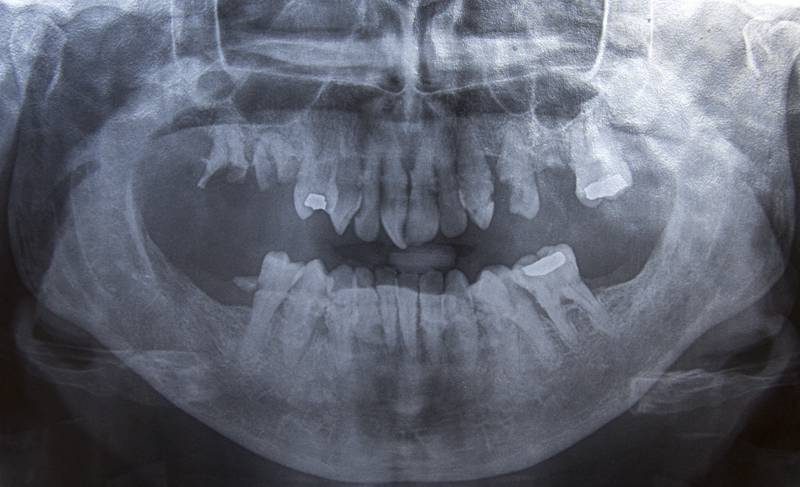

Ok Editing to add the picture of my 45 year old teeth! Ick! As you can clearly see broken molars and some old fillings.